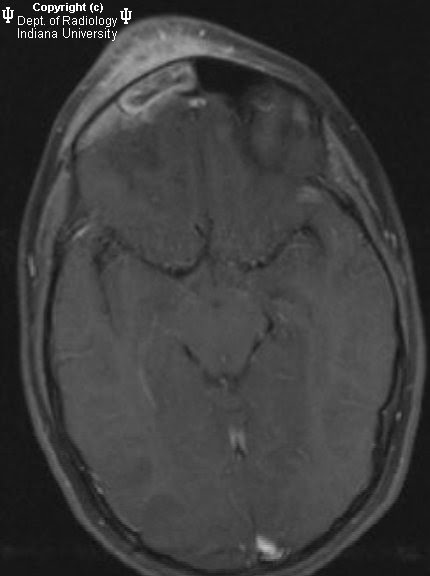

Lessons From Everyday Practice Septic Cavernous Sinus

Neuroradiology On The Net Pott U2019s Puffy Tumor